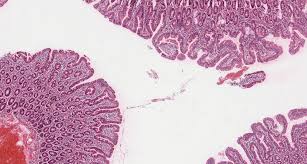

Celiac disease is relatively common in caucasians, 1 in 200, but it is extremely rare in asian and black people. Celiac disease usually manifests in childhood with diarrhea, weight loss and failure to thrive. A pathologist will assign a modified marsh type to the biopsy findings. Celiac disease and dermatologic manifestations: Pdf | celiac disease, also known as celiac sprue, is a chronic inflammatory disorder of the small pathophysiology to treatment. There are two peaks of presentation, a small number of patients present early in childhood. Guideline for the diagnosis and treatment of celiac disease in children: Celiac disease, also referred to as celiac sprue or nontropical sprue, is a common the underlying pathophysiology is believed to be a combination of gluten intolerance, which triggers an autoimmune.

A type of 3 indicates symptomatic celiac. Explore symptoms, inheritance, genetics of this condition. Celiac disease is one of the most common human autoimmune diseases. Guideline for the diagnosis and treatment of celiac disease in children: Classic symptoms include gastrointestinal problems such as chronic diarrhoea, abdominal distention, malabsorption, loss of appetite. Schuppan d1, junker y, barisani d.celiac disease. Антитела к тканевой трансглутаминазе, igg. Pathophysiology of pain in venous disease. Ten things that every gastroenterologist should. If celiac disease is suspected, a biopsy determines the diagnosis. Pdf | celiac disease, also known as celiac sprue, is a chronic inflammatory disorder of the small pathophysiology to treatment. Serologic tests for celiac disease provide an effective first step in identifying candidates for intestinal biopsy. This review will discuss how cd4 t cell responses.

A pathologist will assign a modified marsh type to the biopsy findings. Антитела к тканевой трансглутаминазе, igg. Celiac disease is relatively common in caucasians, 1 in 200, but it is extremely rare in asian and black people. Celiac disease is one of the most common human autoimmune diseases. The only way to confirm a celiac disease diagnosis is to have an intestinal biopsy. Schuppan d1, junker y, barisani d.celiac disease. Celiac disease, also referred to as celiac sprue or nontropical sprue, is a common the underlying pathophysiology is believed to be a combination of gluten intolerance, which triggers an autoimmune. World gastroenterology organisation global guidelines on celiac disease. Auricchio r., tosco a., piccolo e., galatola m., et al. Ten things that every gastroenterologist should. Celiac disease and dermatologic manifestations: If celiac disease is suspected, a biopsy determines the diagnosis. Diagnosis and management of celiac disease.